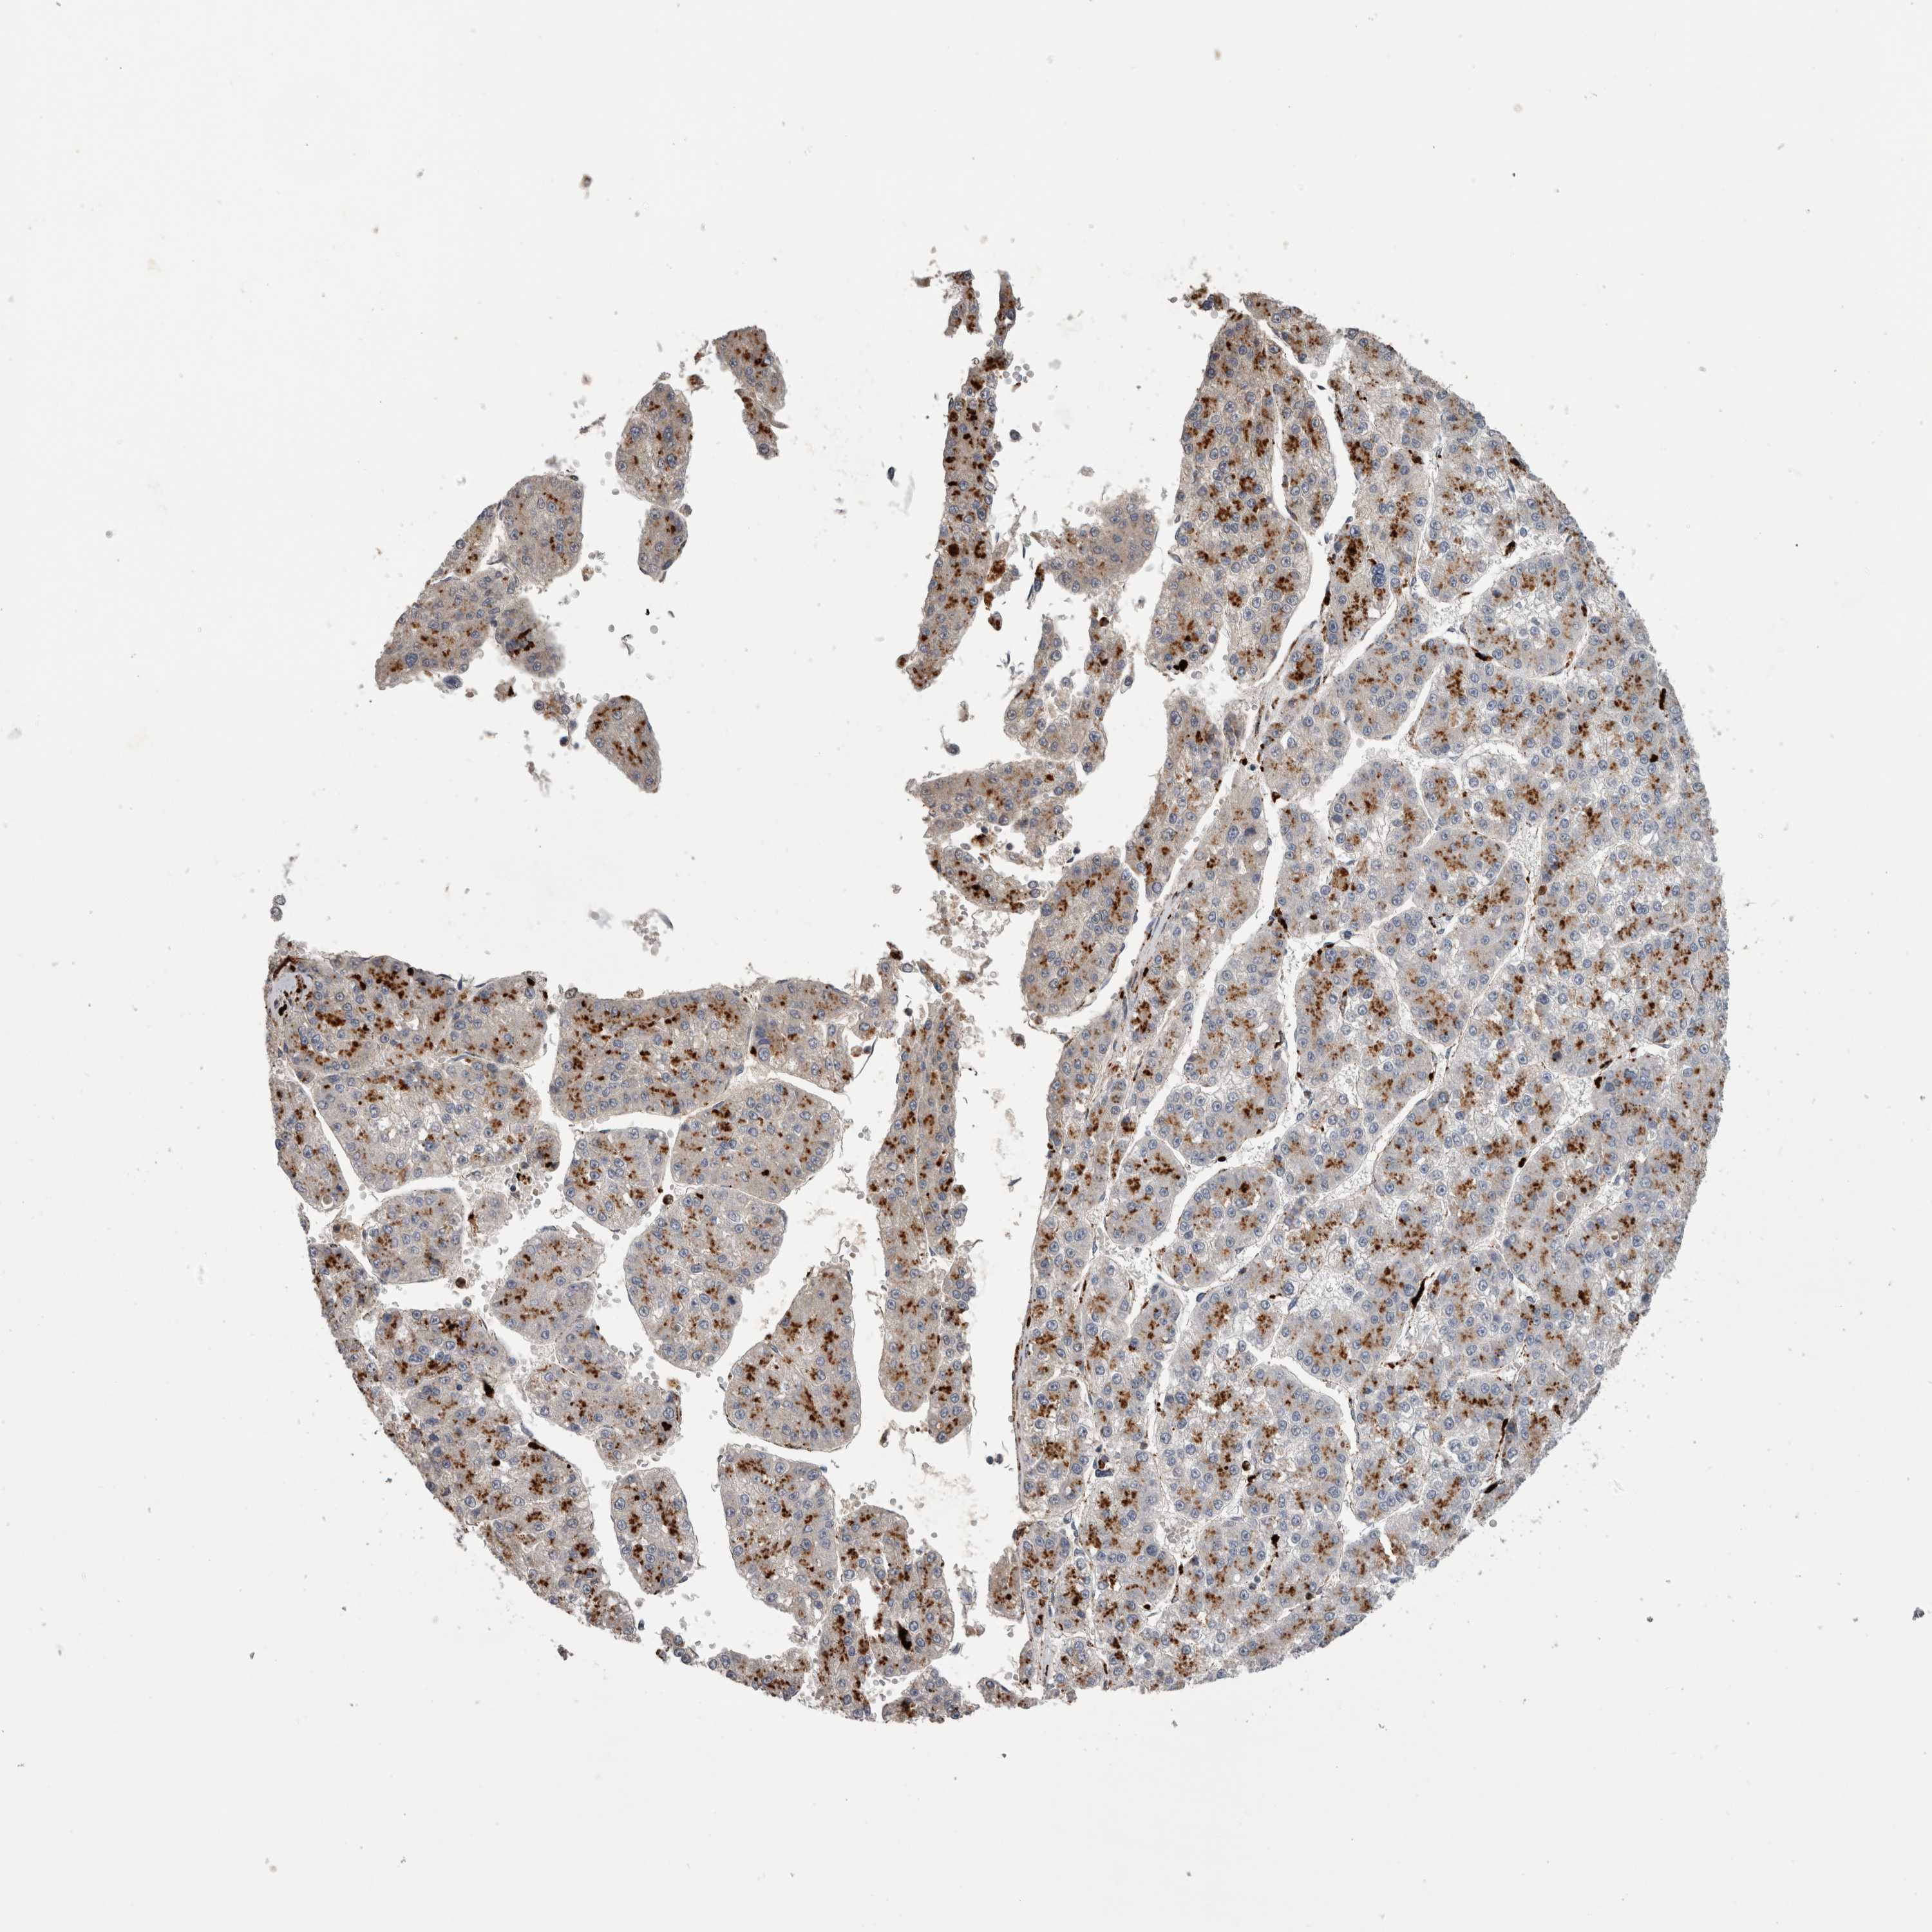

LIVER CANCER - Protein expressioni

A mouse-over function shows sample information and annotation data. Click on an image to view it in a full screen mode. Samples can be filtered based on level of antibody staining by selecting one or several of the following categories: high, medium, low and not detected. The assay and annotation is described here.

Note that samples used for immunohistochemistry by the Human Protein Atlas do not correspond to samples in the TCGA dataset.

Antibody stainingi

Antibody staining in the annotated cell types in the current human tissue is reported as not detected, low, medium, or high, based on conventional immunohistochemistry profiling in selected tissues. This score is based on the combination of the staining intensity and fraction of stained cells.

Each image is clickable and will lead to virtual microscopy that enables deeper exploration of all samples and also displays staining intensity scores, fraction scores and subcellular localization as well as patient and tissue information for each sample.

Antibody HPA049876

Antibody HPA053504

Antibody CAB025114

Staining

High

Medium

Low

Not detected

Intensity

Strong

Moderate

Weak

Negative

Quantity

>75%

75%-25%

<25%

None

Location

Nuclear

Cytoplasmic/membranous

Cytoplasmic/membranous,nuclear

Carcinoma, Hepatocellular, NOS

Cholangiocarcinoma